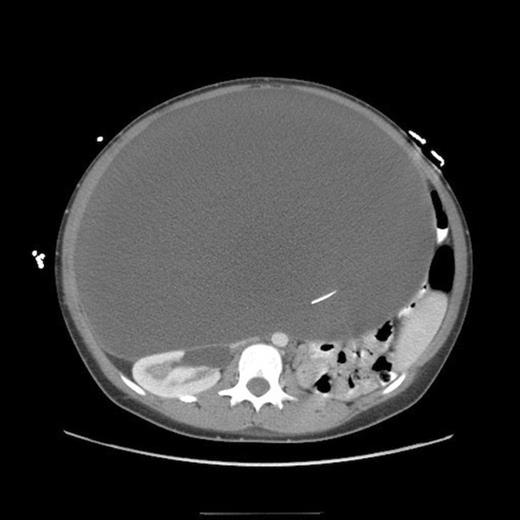

One-month follow up abdominal CT demonstrating recurrent formation of abdominal pseudocyst

The patient underwent laparoscopic cyst drainage with removal of the cyst wall. A total of 12.7L of fluid was drained. Culture results and routine labs were all negative. A post-operative CT demonstrated complete resolution of the fluid compartment (Fig. 4). The VP shunt catheter was initially left in the abdominal cavity. One month later, however, she developed significant recurrence of fluid collection (Fig. 5) and lethargy from malfunction of the VP shunt. The recurrent fluid was drained under ultrasound guidance, and her abdominal shunt catheter was removed. A new shunt catheter was placed in the right atrium, and the patient made a full recovery without any further complications.